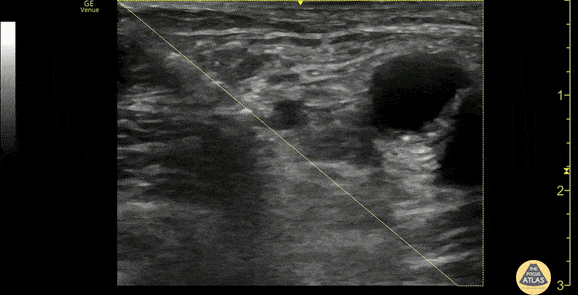

An elderly female with multiple medical comorbidities presented to the ED with hip and thigh pain after a fall at home. Imaging demonstrated an intertrochanteric proximal femur fracture, and, after consultation with Orthopedic Surgery and detailed documentation of the patient’s neurovascular exam, a fascia iliaca nerve block was performed. This clip demonstrates the block, where the needle can be seen entering from the left of screen (laterally) along the trajectory outlined by the yellow diagonal, and anesthetic can be seen infusing just deep to the fascia iliaca and superomedially to the iliacus muscle. The pulsating femoral artery is seen medial to the site of injection. After the nerve block, the patient’s pain was improved and she was admitted for surgical fixation the next morning. Dr. Arian Anderson, PGY-4 and Dr. Michael Heffler, PGY-3 Denver Health Residency in Emergency Medicine